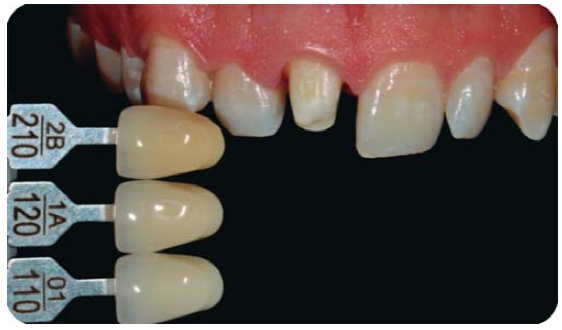

Registro del color

Con el colorímetro Chromascop ® (Figura 23) y provisionalización con resina bisacrílica Protemp 4 ® de 3M (Figura 24), se realiza el cementado de provisional con cemento RelyX Temp ® (3M ESPE), con la finalidad de ir conformando los tejidos previo a la cementación de la restauración final, de igual forma es importante acotar que el registro del color se realiza tanto del muñón de la preparación, como del diente homólogo para que el técnico protesista dental (TPD) tenga mayor información al momento de estratificar y de esta manera crear armonía con la elección de los tonos de las cerámicas a utilizar.

Registro de color y provisionalización

Con el colorímetro VITA classical ® y provisionalización con resina bisacrílica Protemp 4 ® de 3M, se cementa el provisional con cemento RelyX Temp ® (3M ESPE), manejando el tejido previo a la cementación de la restauración final. De igual forma es importante acotar que el registro de color se realiza tanto del muñón de la preparación (Figura 31 A), como del diente homólogo (Figuras 31B y 31C).